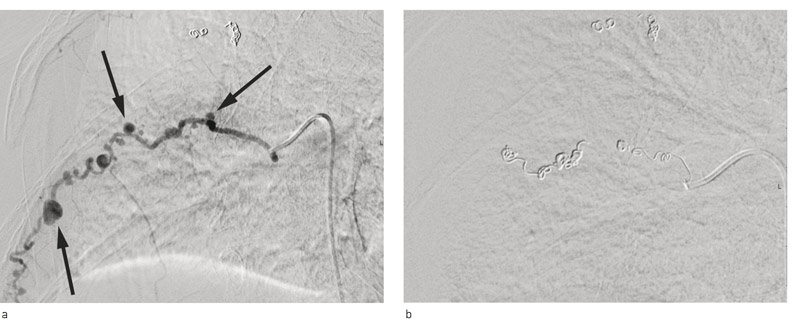

To uker etter operasjonen fikk pasienten en ny blødning, nå fra en interkostalarterie med stor hematomdanning baktil over høyre thoraxhalvdel (fig 1). Kvinnen var takykard, slapp og medtatt. Hun var transfusjonstrengende, men blodtrykksmessig stabil. Pasienten ble på nytt overført til regionsykehus.

Angiografi viste aneurismer på 8. og 9. interkostalarterie på høyre side, og disse ble vellykket coilbehandlet (fig 2). Tre dager etter coilbehandlingen og omtrent to uker etter tynntarmsreseksjonen ble pasienten laparotomert på grunn av høyfebrilia og mistanke om tarmiskemi. Det var imidlertid ikke tegn til iskemi ved peroperativ inspeksjon.